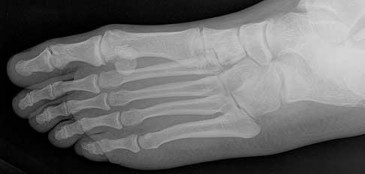

Figures 9a and 9b are the radiographs of a 19-year-old woman with a painful juvenile bunion. The pathologic findings associated with this deformity

The radiographs show a hallux valgus deformity with a laterally deviated distal metatarsal articular surface, a large intermetatarsal angle with medial deviation at the first metatarsocuneiform joint, an elongated medial collateral ligament, and a contracted lateral collateral ligament. There is no distal 1-2 transverse intermetatarsal ligament. The distal transverse ligament in the first interspace extends from the second metatarsal to the lateral (fibular) sesamoid, remains intact, and keeps the sesamoids in a lateral position as the first metatarsal head migrates medially.